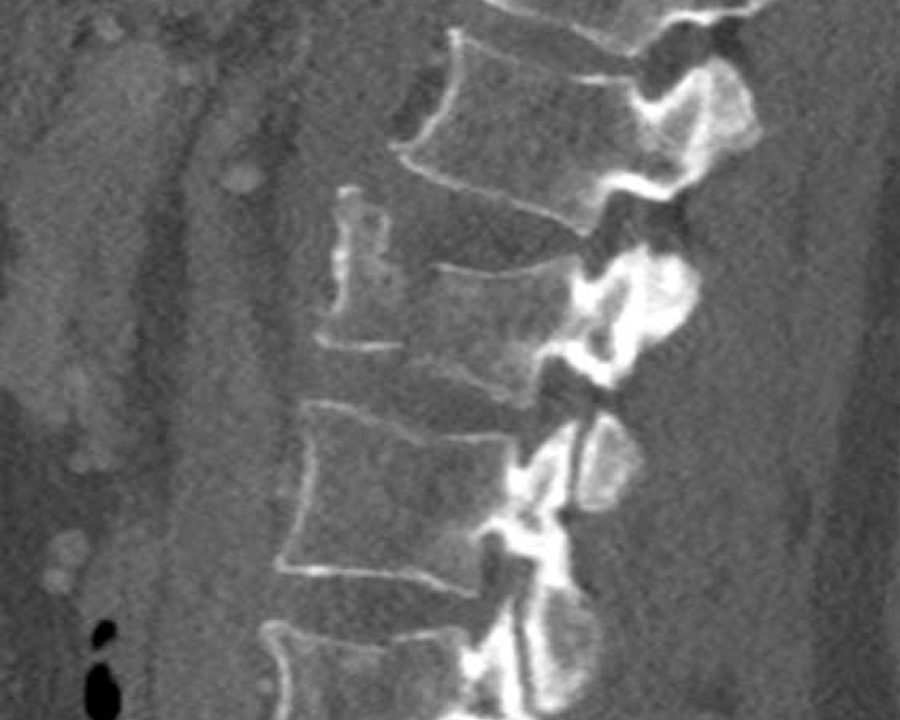

Findings:

- No C or B injury

- Fractures vertebral body with involvement of upper endplate (1 point) and posterior wall (2 points)

Conclusion

Injury type A3